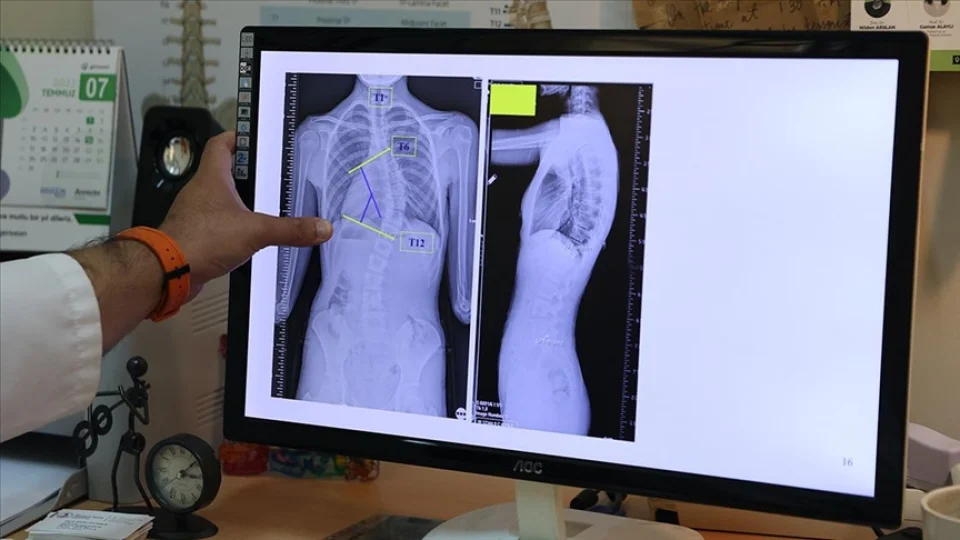

Skolyoz, omurganın yana doğru eğrilmesiyle kendini gösteren bir durumdur. Normalde omurga, arkadan bakıldığında düz bir hat oluşturur; ancak skolyozda bu hat "S" veya "C" şeklinde bozulur. Eğrilik, sadece estetik bir sorun yaratmakla kalmaz, zamanla kaslarda dengesizlik, omuz ve bel ağrıları, hatta ileri vakalarda solunum ve dolaşım sistemlerinde sorunlara yol açabilir.

Skolyoz genellikle çocukluk ve ergenlik döneminde, büyüme çağında ortaya çıkar. Nedenleri arasında genetik faktörler, kas ve bağ dokusu sorunları, doğumsal omurga anomalileri veya nörolojik rahatsızlıklar sayılabilir. Ancak çoğu vakada, kesin neden bilinmez ve bu tür skolyoza "idiyopatik skolyoz" denir.

Belirtileri arasında omuzların veya kalçaların asimetrik görünmesi, bir omuz bıçağının diğerine göre daha çıkık olması, belin tek tarafının daha yüksek görünmesi ve bazen sırt ağrısı yer alır. Skolyozun erken dönemde tespit edilmesi, tedavi başarısını artırır.

Tedavi, eğriliğin şiddetine ve kişinin yaşına bağlı olarak değişir. Hafif skolyozda düzenli takip ve egzersizler önerilirken, orta ve ileri derecelerde korseler kullanılabilir. Çok ileri vakalarda ise cerrahi müdahale gerekebilir. Erken teşhis, skolyozun ilerlemesini durdurmak veya sınırlandırmak için en önemli adımdır.